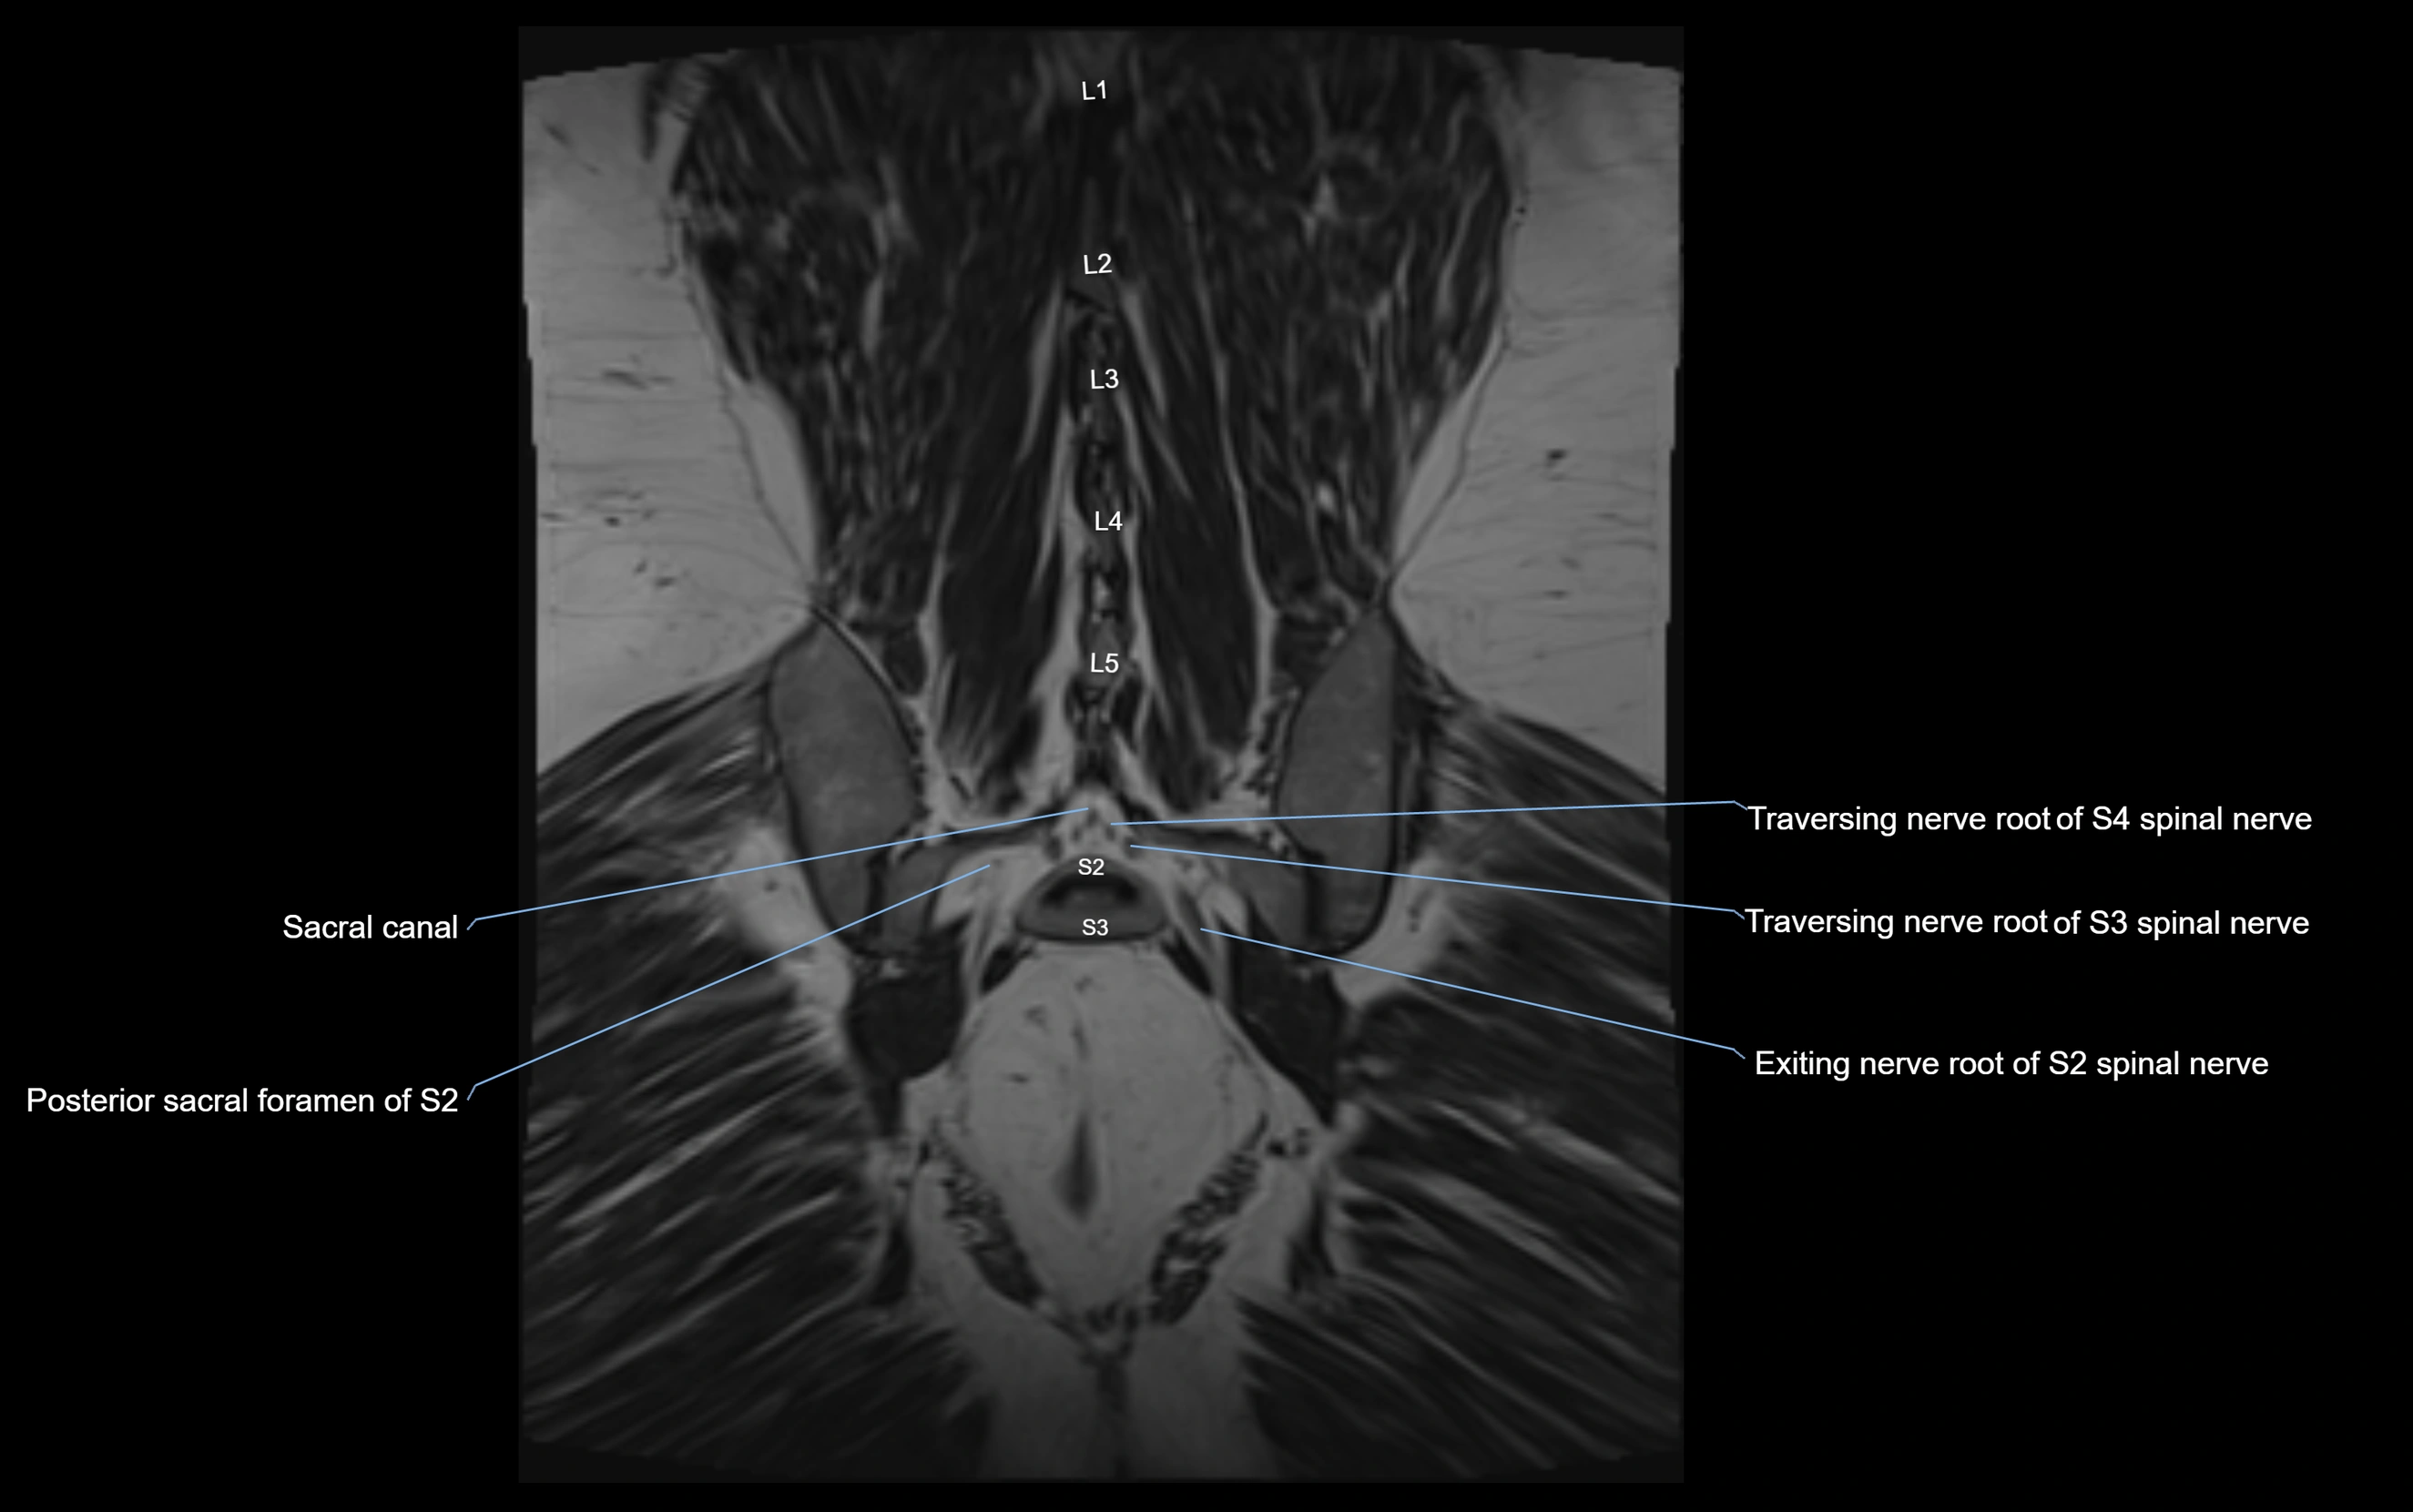

MRI Appearance

T1-weighted images:

• Nerve appears as a very thin low-to-intermediate signal intensity structure

• Surrounded by bright fat, aiding visualization

T2-weighted images:

• Nerve shows intermediate to mildly hyperintense signal compared to muscle

• Pathological involvement appears brighter

3D T2 SPACE / CISS:

• Nerve appears intermediate to mildly hyperintense compared to muscle

• Surrounded by bright fat or CSF, improving visualization

• Best sequence for mapping small pelvic nerves such as the anococcygeal